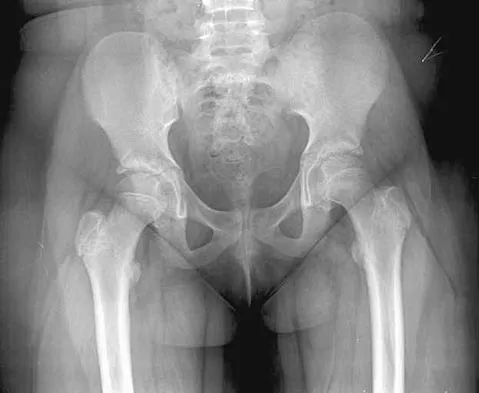

Figure 11 shows the radiograph of a 26-year-old man with type I diabetes mellitus who was struck by a motor vehicle. What is the most common complication associated with this pelvic fracture?

Explanation

The most common complication following acetabular or pelvic ring injury is deep venous thrombosis (DVT). Without prophylaxis, rates of DVT are as high as 70% to 80%. With prophylaxis, the rates are around 10%. Infection rates in surgical repair of acetabular fractures are relatively low but a history of diabetes mellitus and a significant Morel-Lavalle lesion certainly increase the risk. However, even with these two complicating factors, the rates of infection are still lower than 10%. Sciatic nerve palsy rates from the injury alone approach 20% and iatrogenic injury is usually less than 2%. Degenerative changes to the hip following this injury approach 20% to 25%, even with an anatomic reduction. Geerts WH, Code KI, Jay RM, et al: A prospective study of venous thromboembolism after major trauma. N Engl J Med 1994;331:1601-1606.